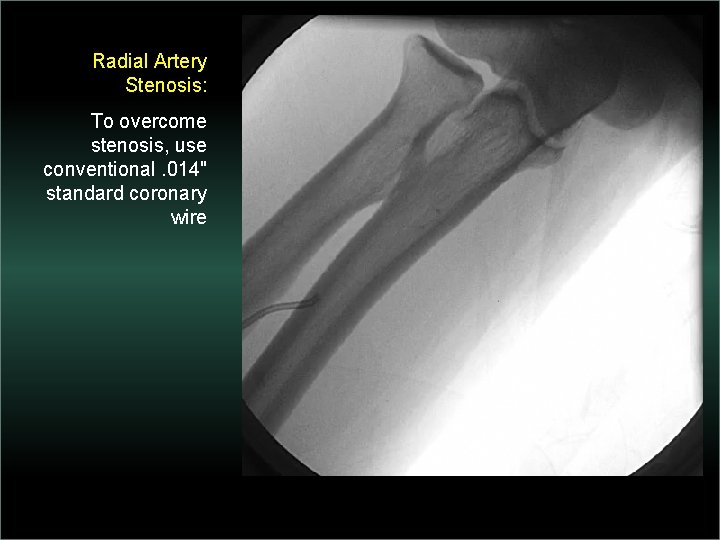

Transradial Interventions Difficult Anatomic Substrate Challenges and Solutions